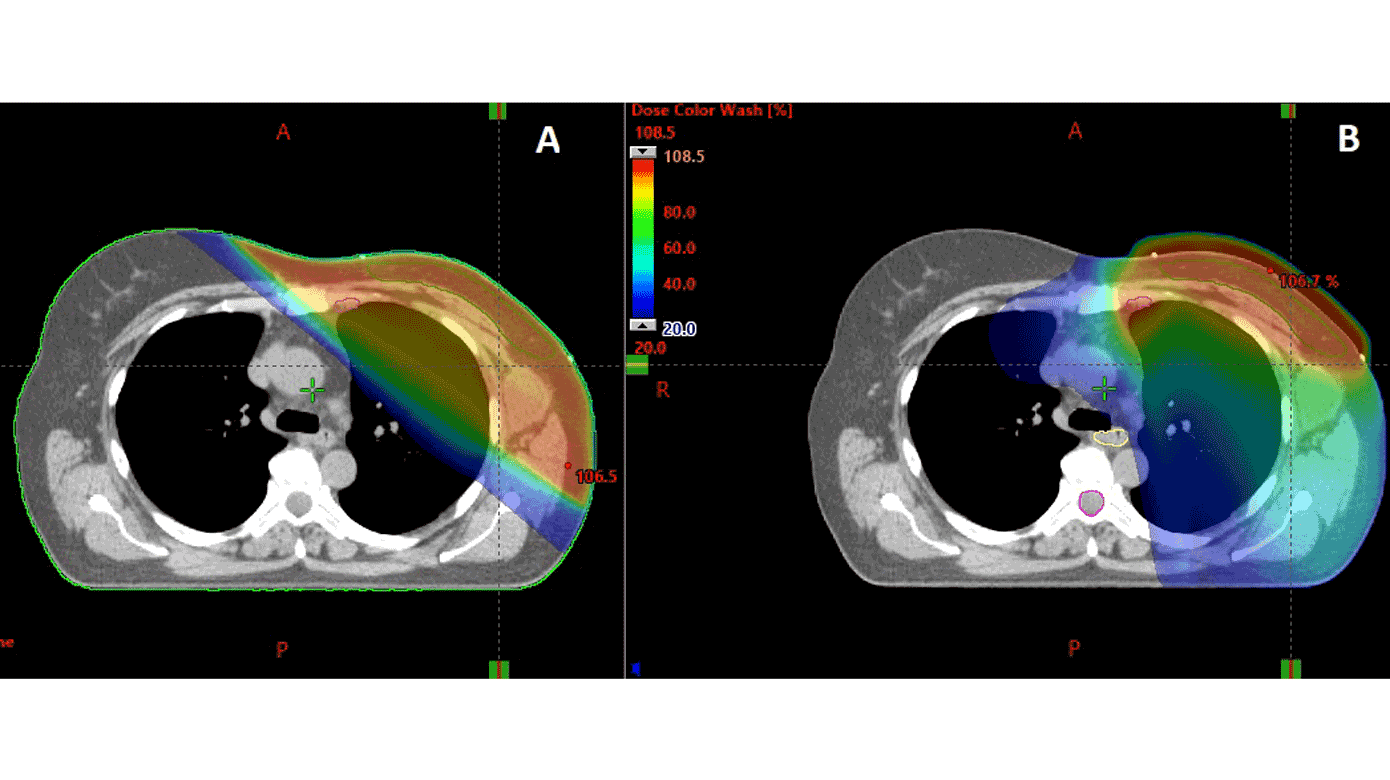

PBI tilbydes patienter med lavrisikobrystkræft, idet lokalt tilbagefald oftest findes inden for den samme kvadrant af brystet, som den oprindelige tumor var lokaliseret i. Ved PBI bestråles kun et begrænset volumen af brystet svarende til området omkring det oprindelige tumorleje (se Figur 1). Dette giver mindre fibrose samt en lavere risiko for senfølger på grund af en reduktion i hjerte- og lungedosis. PBI blev indført i Danmark i 2016 på baggrund af resultaterne fra DBCG’s PBI-studie [7] og det engelske IMPORT LOW [8]. I de to studier blev PBI ikke fundet dårligere end WBI og med en generelt meget lav forekomst af lokalrecidiv. Da der ikke er fundet signifikant højere risiko for tilbagefald ved PBI, taler hensynet til et bedre kosmetisk resultat og lavere risiko for senfølger for anbefaling af PBI hos lavrisikopatienter.

For de få patienter, hvor den planlagte dosis til hjerte og lunger overskrider de anbefalede dosisgrænser, kan brug af moderne planlægning med rotationsteknik være en mulighed. Her omfordeles stråledosis, således at der sikres en mere konform dosisfordeling i højdosisområdet, men til gengæld eksponeres et større volumen af modsatte bryst og lunge, som ellers ikke ville være medbestrålet, for lav dosis (se Figur 3). En anden mulighed er protonbehandling, hvor de anderledes fysiske egenskaber ved protoner potentielt kan forbedre dosisfordelingen. Protonbehandling anses for eksperimentel ved strålebehandling af brystkræft, hvorfor DBCG’s SKAGEN II-studie tilbyder randomisering mellem standardfotonbehandling og protonbehandling til patienter, hvor stråledosis til hjerte og/eller lunger overskrider de anbefalede dosisniveauer.